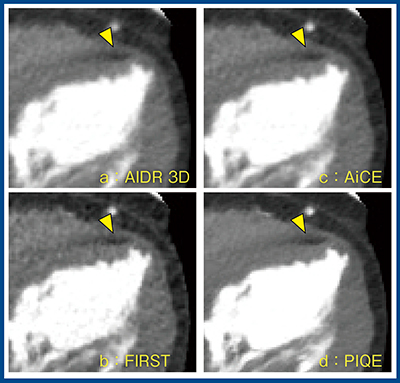

図8は陳旧性心筋梗塞症例で,心尖部に小さな梗塞を認める(▼)。すべての画像で梗塞を指摘できるが,PIQE(d)ではノイズが大きく低減され,梗塞部がより明瞭である。

図8 陳旧性心筋梗塞の描出